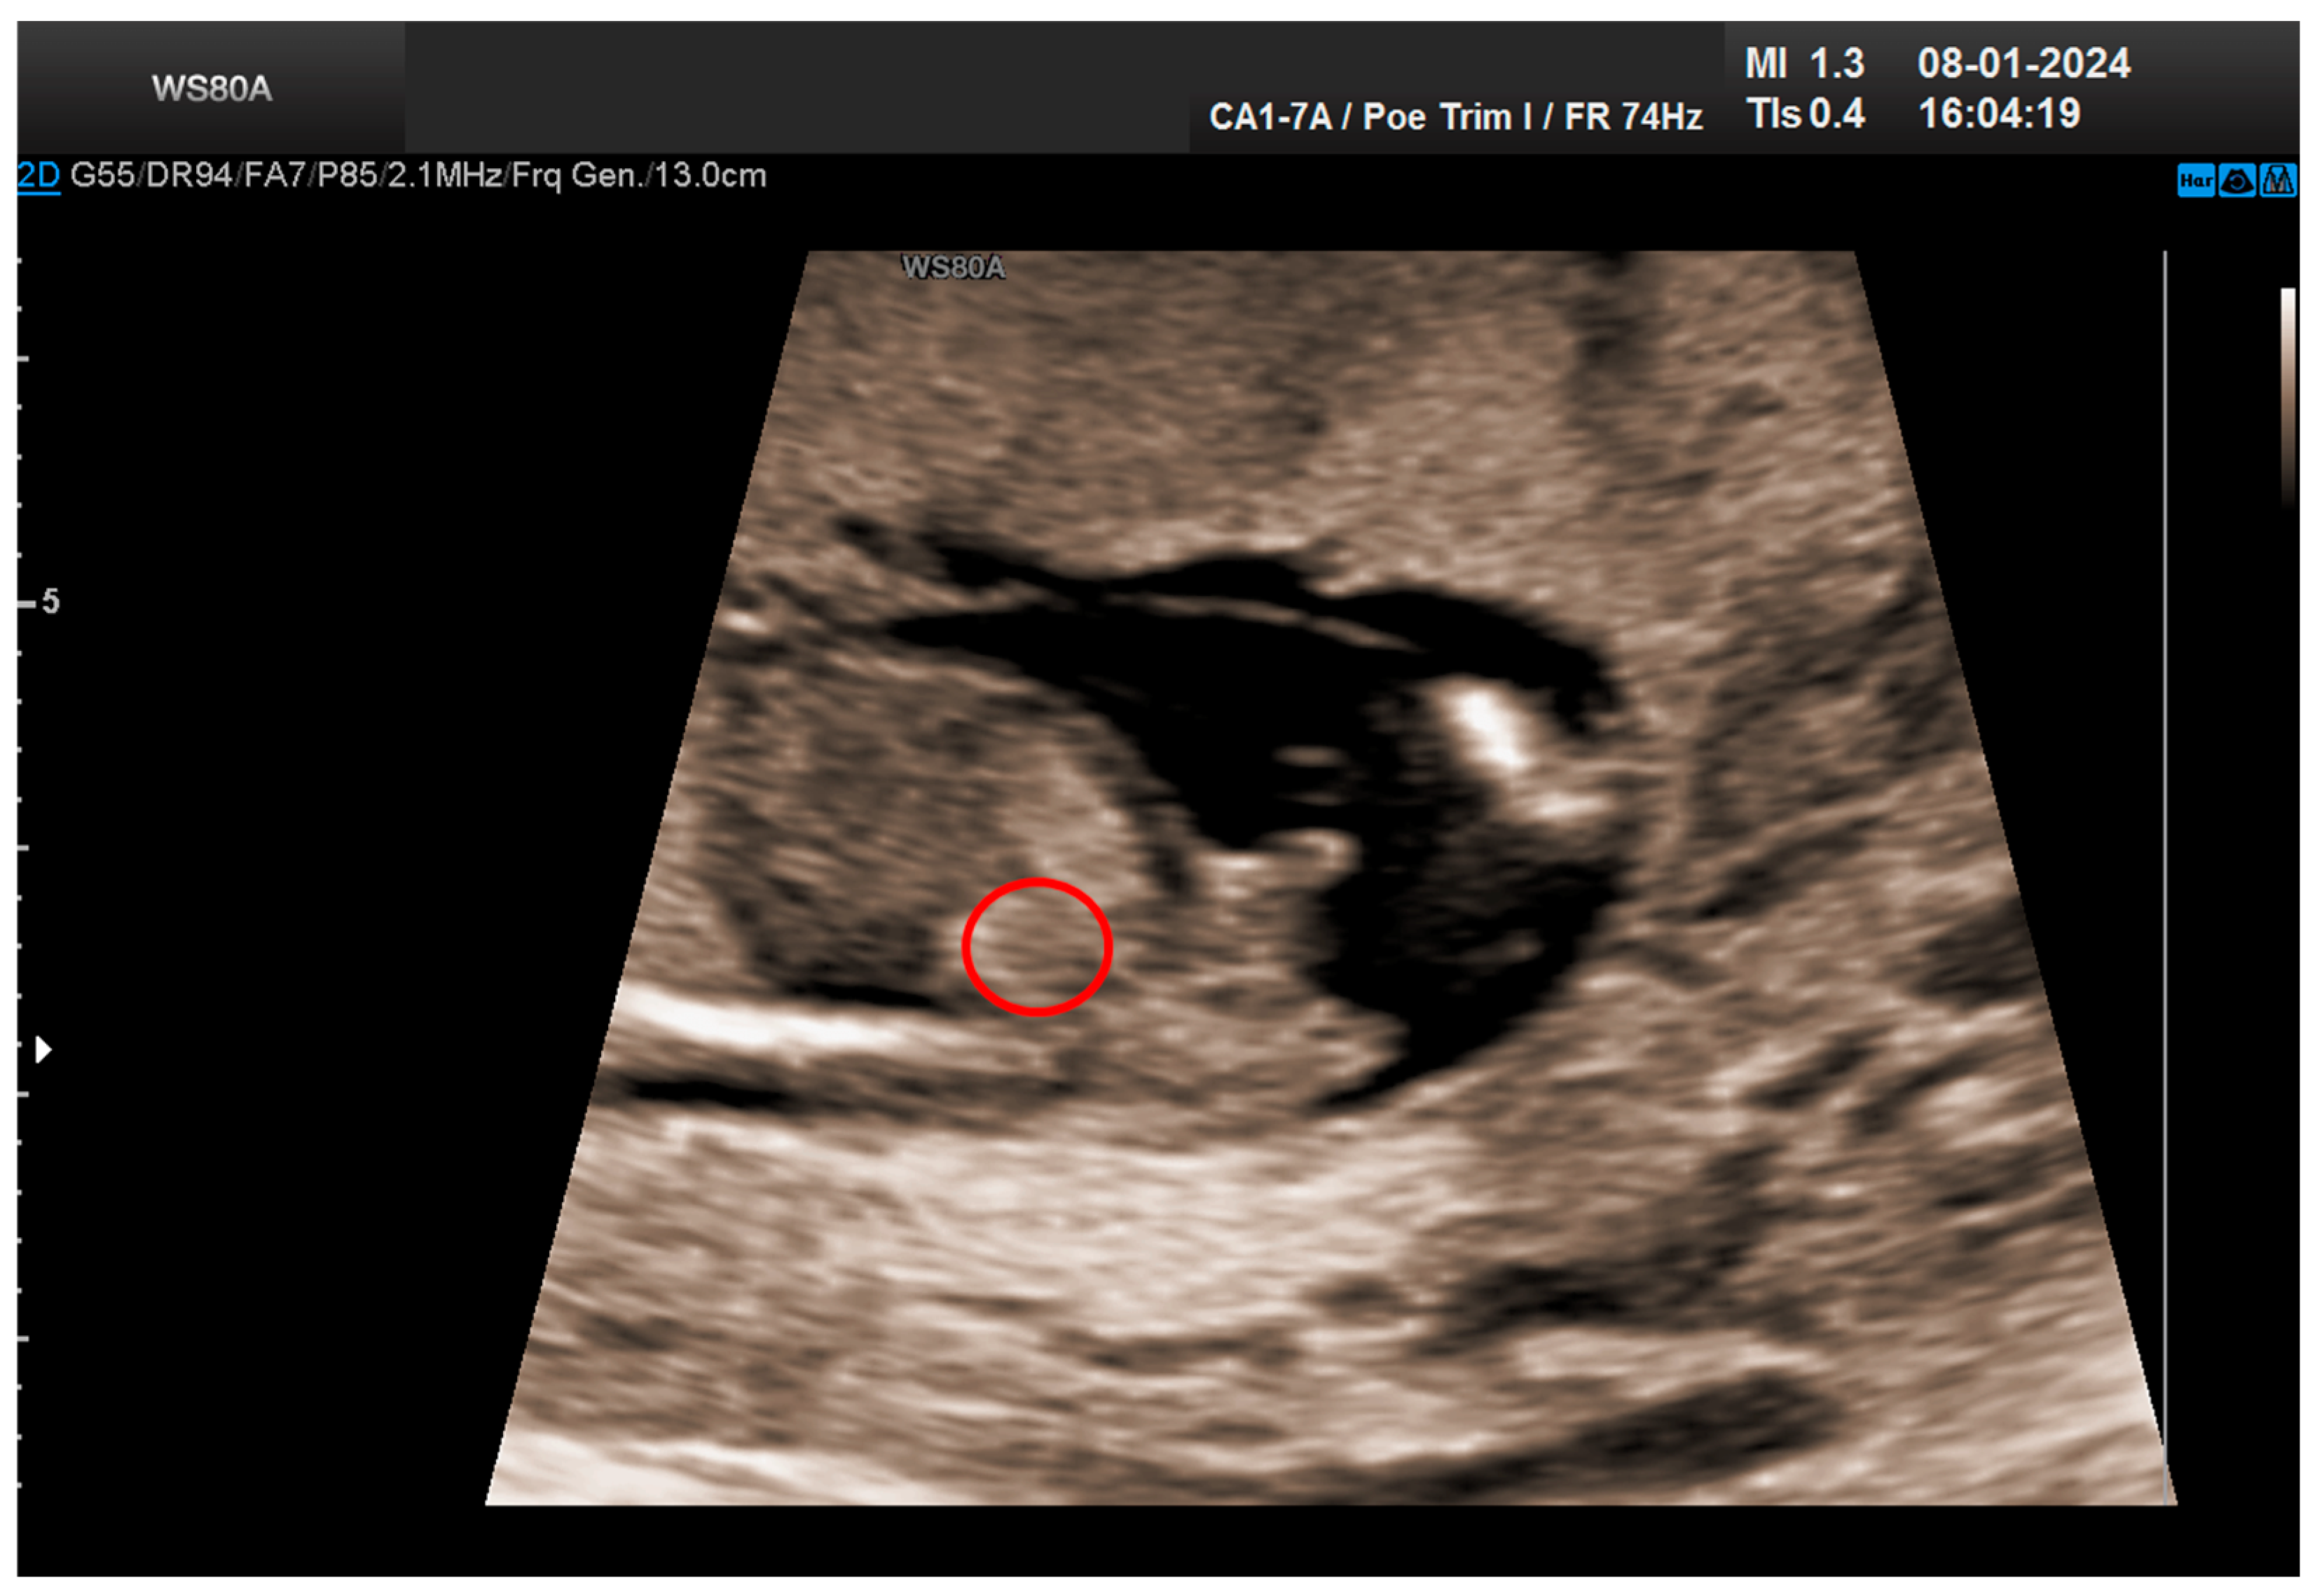

The combined test result indicated a low risk for trisomies, preeclampsia, and intrauterine growth restriction. However, during the ultrasound examination, the absence of the right renal tissue in the right parasagittal sections was noted (Figure 1). Examination of the embryo in axial sections demonstrated the presence of a relatively well-defined acoustically heterogeneous echogenic mass situated anterior to the spine, in sonographic contact with the renal tissue image correctly occupying the left lumbar fossa (Figure 2). Those aspects suggested the existence of a renal anomaly of crossed fused renal ectopia. No other embryonic anomalies were detected, the bladder image was present, and the amniotic fluid volume was normal. The calculated gestational age corresponded to the ultrasound estimate. The suspicion of crossed fused renal ectopia was maintained during a subsequent reevaluation at 17 weeks of pregnancy (Figure 3 and Figure 4).

Figure 2. Crossed fused kidneys at 13 weeks.